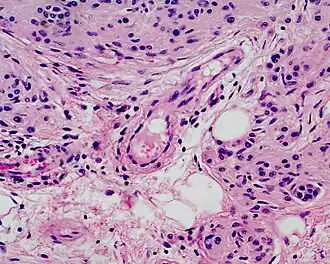

Un nævus congénital mélanocytaire est une tumeur bénigne. Il est composé d’une très grande collection de cellules pigmentaires (mélanocytes) dans une zone délimitée de la peau. Les mélanocytes ont comme origine embryologique la crête neurale[1]. Ces cellules migrent vers la peau et colonisent à peu près tous les tissus du corps[2].